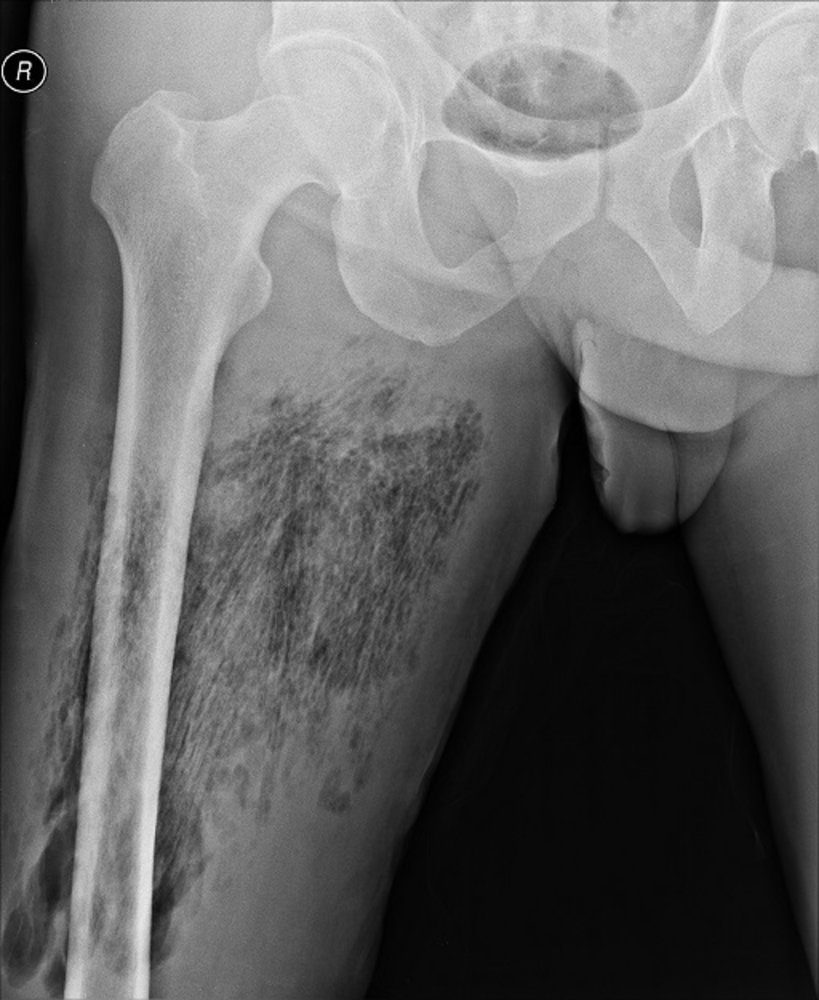

Prolonged Acute Kidney Injury and Symmetrical Peripheral Gangrene: A Rare Case Report of Acute Promyelocytic Leukemia